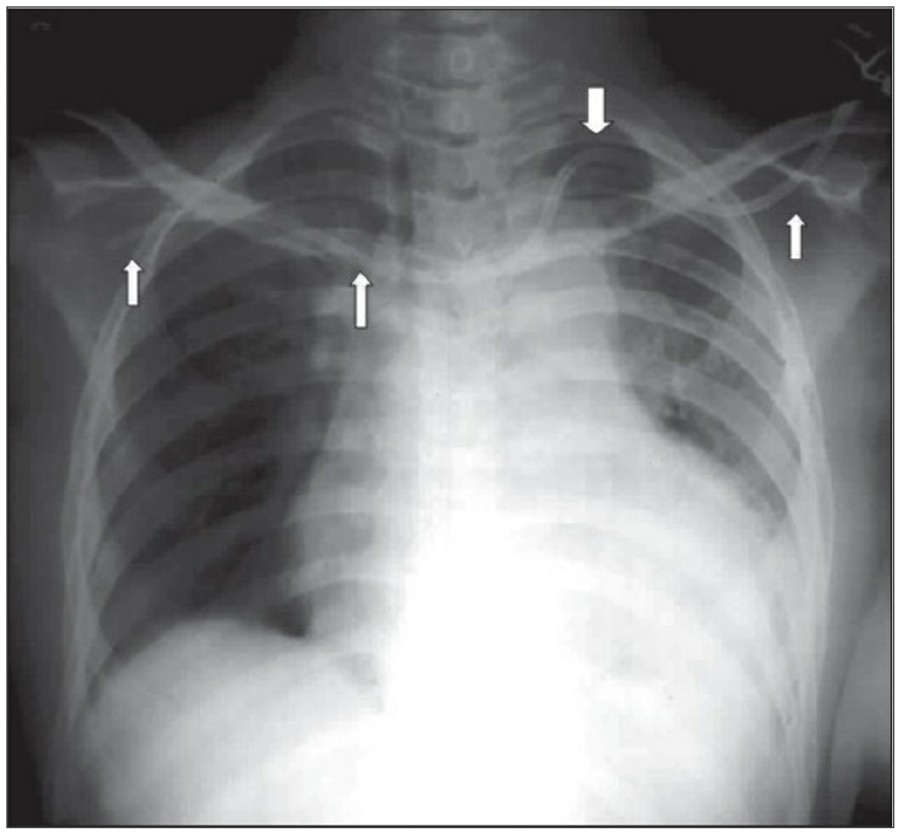

Subcutaneous emphysema는 드물지 않으며 주로 drain이나 다른 device의 percutaneous intrathoracic placement 시 발생한다. Fascail plane을 따라 air dissection이 발생하는데 임상적으로 의미가 없는 경우가 많다.

Subcutanoeus emphysema는 pneumomediastinum과 관련이 있을 수 있다. 하지만, isolated cervical subcutaneous emphysema가 있을 경우에는 upper airway 손상에 대한 평가가 필요한데, 특히 difficult intubation이나 nasogastric tube insertion 후에 발생할 수 있다. Chest X ray 상에서 subcutaneous emphysema 소견은 명확하다; 하지만 주로 pectoralis region의 muscle bundle 사이에서 발생하는 fascial plane의 air dissection은 lung prehncyme의 변화를 가리곤 하며, pneumothorax의 발견도 어렵게 만든다.